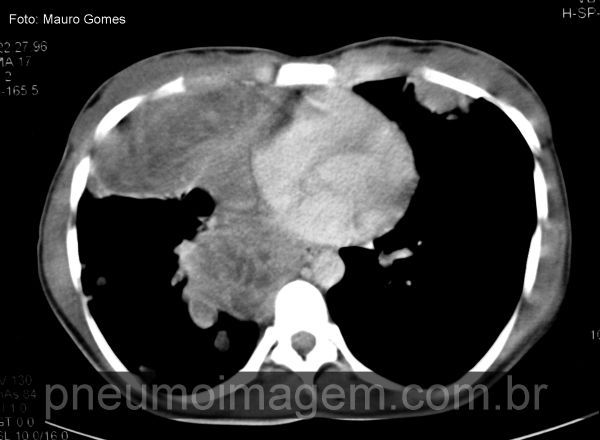

Massa que se estende desde o mediastino médio até o mediastino anterior, comprometendo a parede torácica anterior, e com áreas centrais de necrose. O PPNET da área toracopulmonar é frequentemente denominado tumor de Askin. Chaves: Askin tumor.

Detalhe do pulmão esquerdo mostrando os numerosos nódulos pulmonares. Dependendo do grau de diferenciação neural, esses tumores são denominados Sarcoma de Ewing, quando é um tumor indiferenciado, ou Tumor Neuroectodérmico Primitivo Periférico (PPNET), quando apresenta características de diferenciação neural.

A família de Tumores de Ewing compreende um espectro de neoplasias de células neuroectodérmicas primitivas, que são células embrionárias que migram da crista neural.